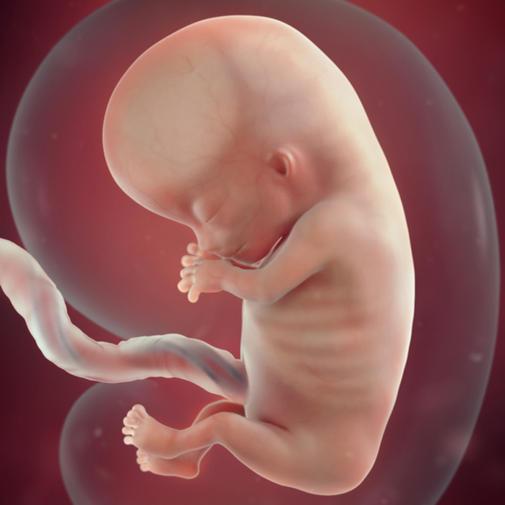

11. týden těhotenství začíná vaše miminko rychle růst do délky, začínají mu vyzrávat vnitřní orgány. Až do termínu porodu se také pozvolna mění proporce celého těla i jeho jednotlivých částí. Všechny vývojové procesy probíhají plynule, takže změny vzhledu plodu již nejsou tak dramatické, jako v prvních týdnech. Na druhé straně mezi nástupem jednotlivých procesů mohou být při srovnání i určité individuální časové rozdíly. Výsledkem všech dalších vývojových procesů je, že od konce embryonálního období roste vaše budoucí miminko "do krásy".

Na začátku třetího lunárního měsíce je hlava plodu stále hodně velká, téměř stejně velká jako celé tělíčko. Kolem mozku i v hlubších vrstvách obličeje se postupně formují hutnější chrupavčité a kostěné základy lebky. Zřetelné začínají být také zpočátku drobné svaly.

Obličej je stále rozsahem velmi malý, jeho rysy se začínají zjemňovat. Za očními víčky, která spolu rychle srůstají, prosvítají vyvíjecí se očička. Oči nemají dosud založeny všechny své budoucí součásti. Díky pigmentu v sítnici se jeví jako tmavé kulaté terčíky.

Obličej plodu se začíná s určitými odlišnostmi podobat lidskému. Uši jsou nízko posazené, oči jsou daleko od sebe, překryty srostlými očními víčky. Tvoří se většina kloubních spojení jako například kotníky či zápěstí. Pokračuje vývoj trávicí soustavy. Vyvíjejí se zárodky smyslů, zejména čichu, sluch ještě nějakou dobu nebude vyvinutý. Prsty na nohou i rukou jsou oddělené, ale jsou velmi drobné. Pro představu: chodidlo vašeho děťátka teď měří asi 2,5 mm. Plod je nyní asi 44 až 60 mm dlouhý, má něco kolem 8 gramů váhy. Vaše miminko má za sebou kritickou fázi vývoje. Nyní už riziko vzniku vývojových vad nebo poškození infekcemi či léky není tak velké.

V 11. týdnu těhotenství měří plod zhruba 4,0 cm .Při zjišťování délky plodu se měří vzdálenost od temene ke kostrči. Plod nyní váží zhruba 7 gramů.